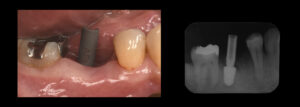

オペから10週後、セラミックの歯をセットして、治療は完了です。